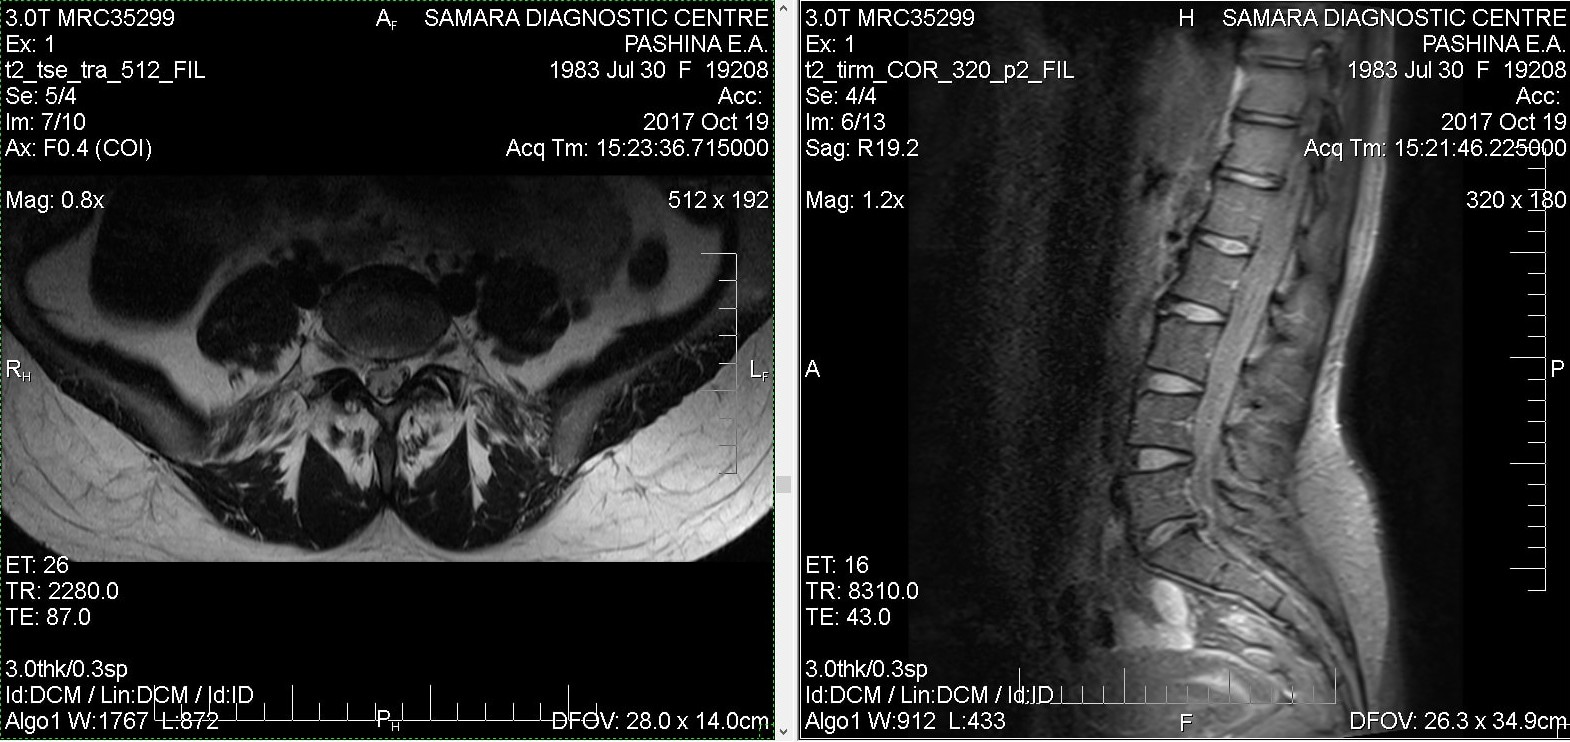

Тренировки с межпозвоночной грыжей.